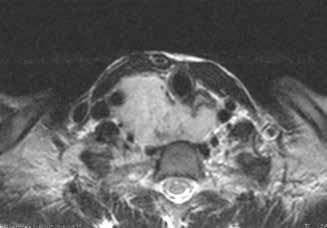

The diagnostic workup included computed tomography (CT) and magnetic resonance imaging (MRI), which clearly demonstrated the bilateral masses in the maxillary sinuses (figure 1). Because of the atypical bilateral presentation of the mucocele, we also performed electron microscopy to examine sinonasal mucosa tissue samples. This analysis revealed an absence of one of the microtubule doublets in three of the outer doublets of the axoneme (figure 2). To rule out etiologies such as cystic fibrosis and Kartagener syndrome, we obtained a chest x-ray and performed a chloride-in-sweat test; findings were normal. Our final diagnosis was isolated ciliary dysfunction.

Figure 1. A: Coronal CT shows the homogeneous isodense soft-tissue mass occupying both maxillary sinuses with bone remodeling of their walls, including the orbital floor. B: Axial T2-weighted MRI demonstrates the hyperintense cystic masses in both maxillary sinuses and the expansion of the orbital floor.